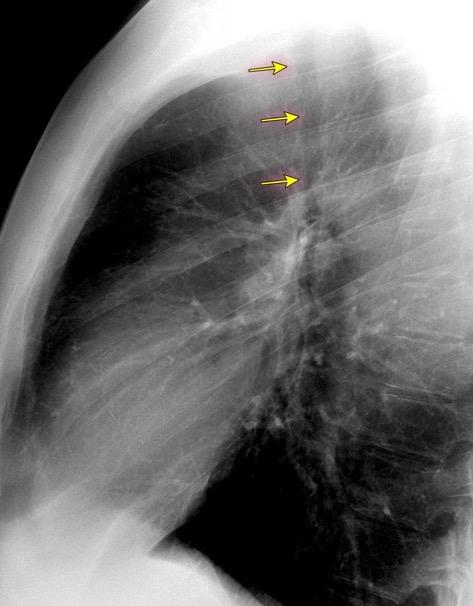

Triada de Garland

Ganglios paratraqueales derechos e hiliares bilaterales

95% de pacientes tienen ganglios hiliares bilaterales aislados o con afectación mediastínica (espec. paratraqueal derecho).

Criado E et al. Pulmonary sarcoidosis: typical and atypical manifestations at high-resolution CT with pathologic correlation. Radiographics. 2010